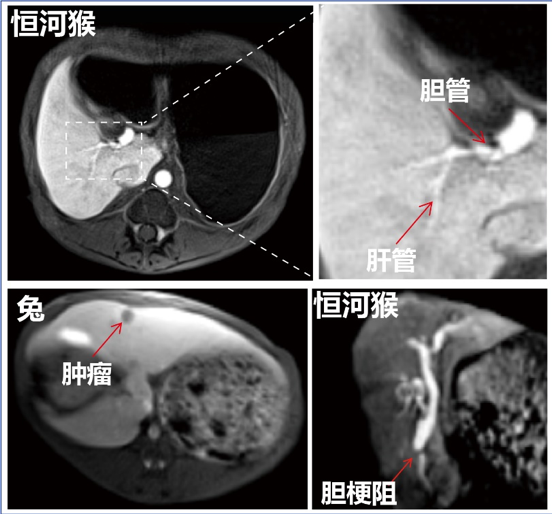

研究结果表明,MnFe2O4纳米颗粒表面的Mn离子和其表面修饰的乙氧苯(EOB)配体可实现对肝细胞SLC39A14和OATP1的双靶点协同靶向作用,显著提升了特异性和亲和力,活体(猪)实验显示其肝细胞特异性分布可高达70.59%。猴、猪等大动物实验肝胆成像结果显示,与临床Gd-EOB-DTPA相比,可使肝对比度增强5.8倍,并可高清晰分辨0.5毫米的肝管。同时肝实质和胆管显像速度也提升了2倍以上,显著减少患者检测时间,提高了检查效率。活体肝癌成像结果显示,该对比剂可将微小肝癌病灶(<0.5厘米)的检出率从48%提高至92%,并可清晰判断胆梗阻位置与梗阻程度,有望用于无创胆管成像。初步非临床GLP评价和大动物安全性评价结果均显示出良好的安全性,可通过肝、肾快速清除,7天残留率小于1%,具有极好的临床转化潜力。该研究双靶点设计的新型肝细胞特异性准顺磁纳米对比剂为肝癌早期发现提供了新的影像诊断工具。MnFe2O4-EOB-PEG已注册商标“玵立显”,目前在西安超磁科技进行临床转化研发。

MnFe2O4-EOB-PEG纳米对比剂磁共振肝胆成像